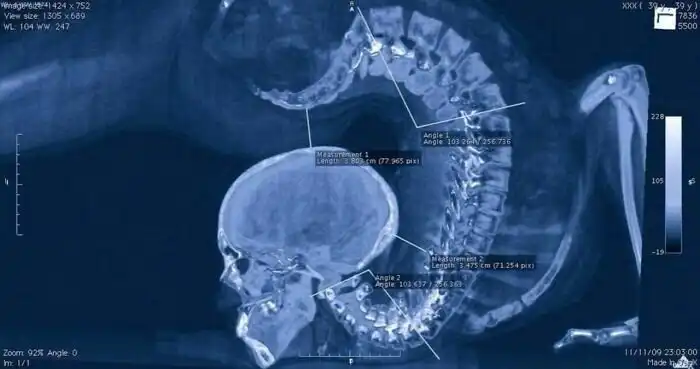

Рентгеновский снимок гимнастки во время выполнения упражнения